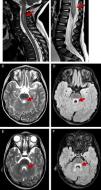

En todos los casos se realizó punción lumbar, mostrando en 9/11 pleocitosis en el líquido cefalorraquídeo (LCR) de predominio linfocitario (7/11). Se realizó RM en 10 pacientes, objetivando en 8/11 rombencefalitis, con asociación de mielitis en 7/11 y mielitis aislada en 2/11 (fig. 1). Debido al alto porcentaje de pacientes con somnolencia e irritabilidad se realizaron 10 electroencefalogramas (EEG) mostrando trazado enlentecido en 9. Resultaron normales los 9 potenciales evocados auditivos de tronco cerebral realizados por afectación de tronco del encéfalo en RM o clínica bulbar, así como los 3 electromiogramas por afectación medular extensa.

RM potenciadas en T2 y en FLAIR con afectación de rombencefalomielitis. Aumento de señal en T2 de la médula cervical hasta C6 en paciente 2 (A) e importante engrosamiento del cono medular en paciente 4 (B). Hiperintensidad en T2 y en FLAIR en la región posterior de la protuberancia, rodeando al cuarto ventrículo (C-F) en paciente 2.